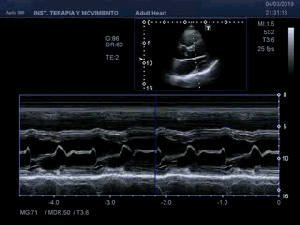

139. Ecocardiografía. Estudio Paraesternal Eje Largo.

141. Mediciones de los planos paraesternales.